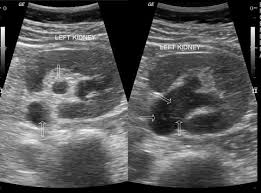

Kidney Ultrasound Emergency Medicine. Found that in the diagnosis of renal calculus the sensitivity of renal ultrasound alone was 93 and specificity 83. A landmark study published in 2014 by the new england journal of medicine conducted at 15 various emergency departments evaluated the accuracy of point of care ultrasound pocus versus computed tomography ct scan as the initial imaging method for patients with suspected kidney stones.

This has been studied formally in both emergency medicine and perinatology and in both cases there were no legal actions related to misdiagnosis. In our 20 years of experience with point of care ultrasound by nephrologists at this institution entailing over 20 000 studies this issue has not arisen once. In the emergency department bedside renal ultrasound has allowed the physician to quickly and accurately assess the kidneys and the bladder for obstruction.

Furthermore patients with a normal renal ultrasound are at low risk for hospitalization or urologic intervention 1 3.